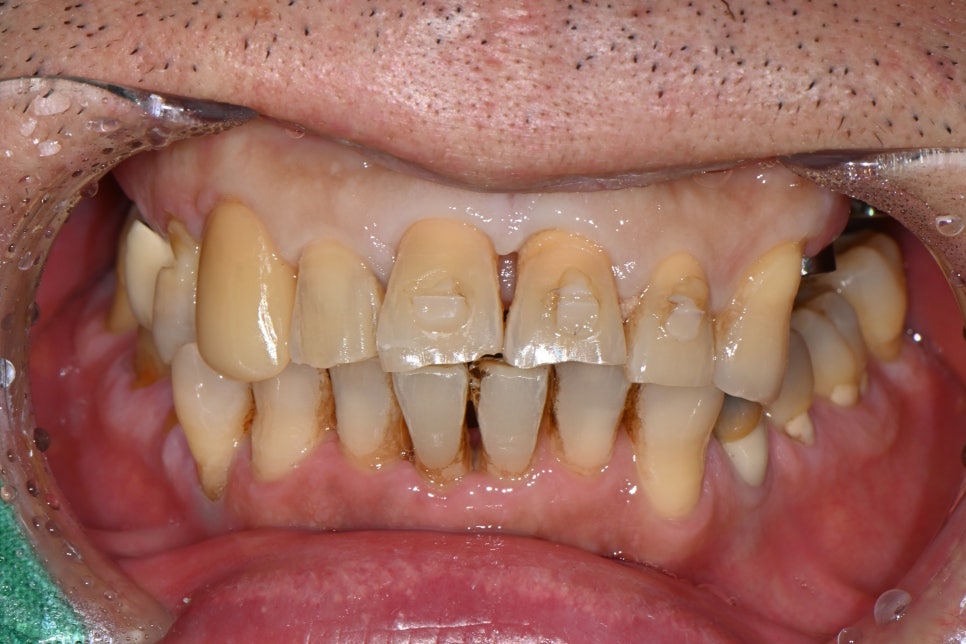

🖼️ After lip and gum recovery / Front view after the fixation device on the front tooth was removed

Front view photo after stitch removal

🦷 Restoring a natural smile with a prosthesis for the front tooth

After root canal treatment was completed, the front tooth was finished with an esthetic prosthesis in collaboration with our in-house dental technician.

It was made in a natural color and shape that was almost indistinguishable from the existing teeth,

and because it did not look noticeable even when smiling, the patient was very satisfied.